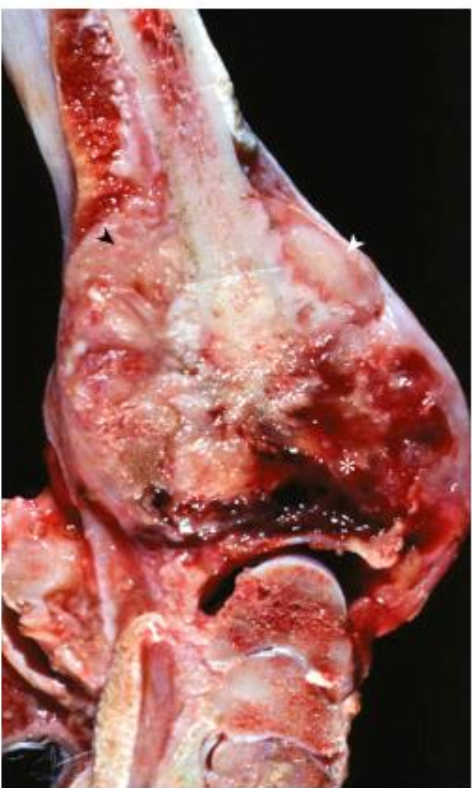

What is affecting this canine distal radius? note the reactive periosteal new bone formation and the large area of hemorrhage and necrosis.

osteosarcoma